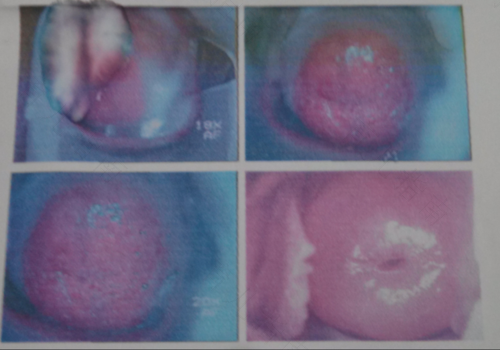

众所周知,妇科炎症是只有女性朋友们会患上的病症,而在这之中,宫颈糜烂是很多女性都遇到过的问题。相信在发现这个问题的时候,有些女性朋友还是会比较慌张,特别是刚刚成年不久的女性,那么,22岁宫颈糜烂怎么办呢?

其次,严重的宫颈糜烂也是大问题,此时应当去医院进行相关的检查,看看是否为比较轻度的宫颈糜烂。如果是正常的就没什么后顾之忧,只需要买点消炎药吃一下就可以,再买点专门的洗液清洗外阴,将自己的内衣内裤清洗消毒。

另外,严重的宫颈糜烂如果不及时治疗,往往还会引起各种病变,如果变成了癌症就会变得很难治疗了。随意,拖着不治疗肯定是不好的,要及时进行检查。